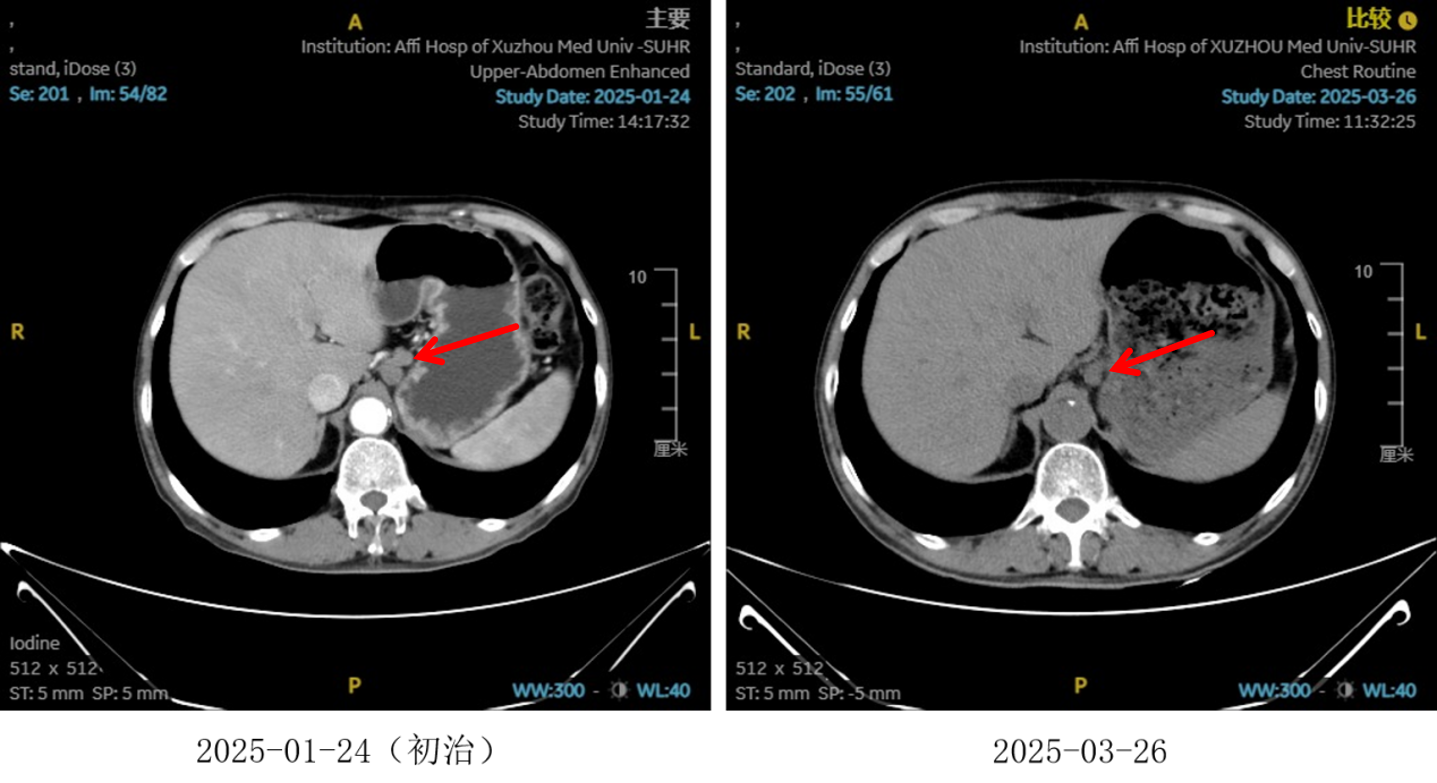

图5:4、6周期化免靶后食管癌病灶对比

图6:4、6周期化免靶后淋巴结对比

图7:4周期治疗后影像学 [图左:“食管Ca化疗后”,食管胸中下段管壁增厚,较厚处管壁约12mm,边缘模糊,病灶局部与邻近大血管、气管壁分界不清。图右:纵隔内(3P、4、7)、左肺门示稍大淋巴结影。]

图8:6周期治疗后影像学 [图左:“食管Ca化疗后”,食管胸中下段管壁增厚,较厚处管壁约10mm,边缘模糊,病灶局部与邻近大血管、气管壁分界不清。图右:纵隔内(3P、4、7)示小淋巴结影。]

疗效评估

治疗2周期后,食管壁厚度由17mm降至15mm,淋巴结由18mm×15mm缩小至16mm×13mm;4周期后,食管壁进一步缩至12mm,淋巴结明显减少;6周期后,食管壁仅余10mm,纵隔内仅见小淋巴结影,疗效评估“接近CR”。